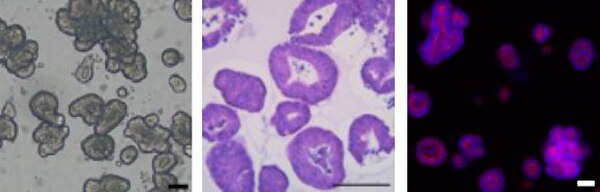

SCC503 Sigma-Aldrich3dGRO™ Human CRC Organoids (ISO49)

| Application | Ready-to-Assay human colorectal cancer organoids for 3D cell culture applications. |

| Material Size | ≥ 100,000 organoids/vial |